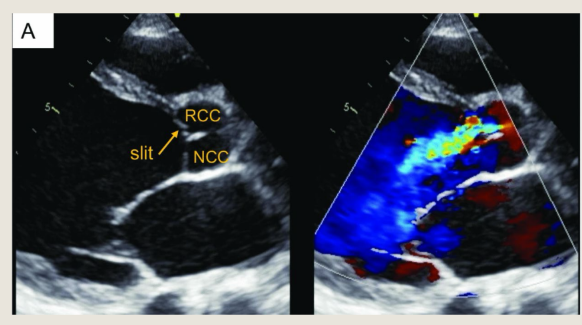

which one is central VS eccentric AR

Central is the 1st pic

eccentric is the 2nd pic

AR via color flow may be unreliable due to what

Unreliable due to

diastolic blood pressure

and acute AR